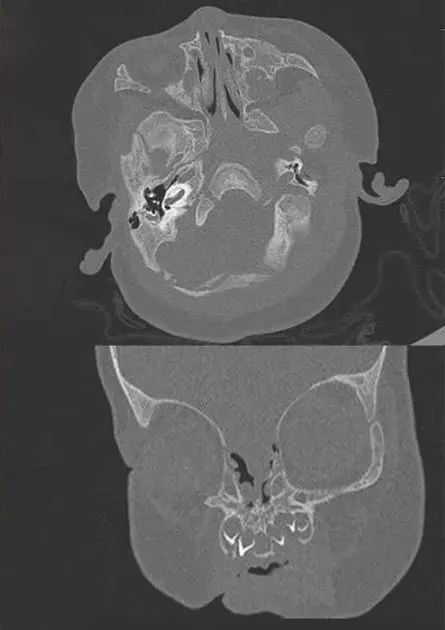

患儿鼻部CT影像。图片来源:中山医院团队